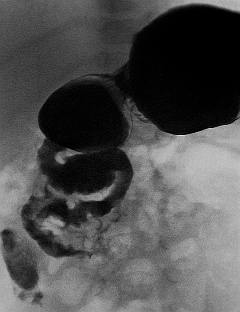

In midgut volvulus there may be a bird's beak cut-off of contrast in the second portion of the duodenum, or the duodenum may have a corkscrew appearance if contrast can get into the loops of bowel that have twisted.[Figure caption and citation for the preceding image starts]: Malrotation with volvulus without obstruction as seen on upper GI contrastFrom the collection of Dr S.D. St Peter [Citation ends].